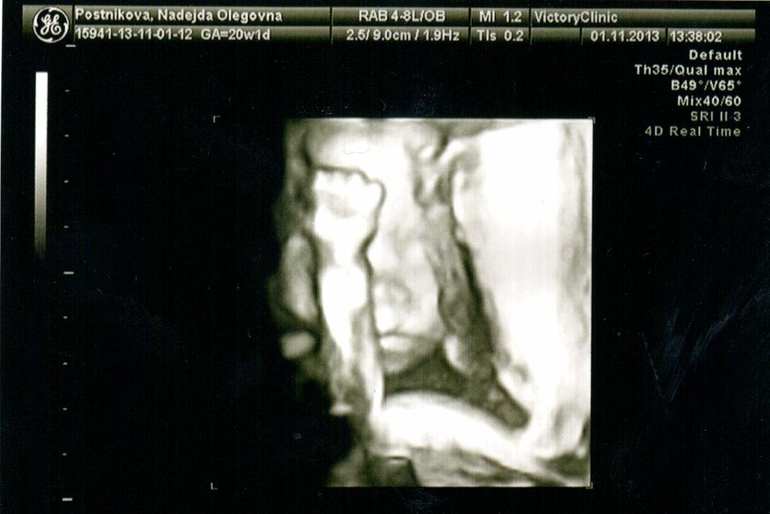

Сегодня я по особенному счастливая и наш с пузиком экватор - не единственная тому причина, причин у нас много - сегодня мы были на УЗИ (подглядывали за нашим сокровищем), до сих пор эмоции переполняют… :) У нас все хорошо, развиваемся по сроку, уже довольно-таки большие - 330 грамм )) Мы узнали пол, я аж прослезилась от счастья ))) Муж тоже очень рад, от чего я счастливее вдвойне )))

Собственно говоря, вот и мы:

На УЗИ мы спали, так что выкрутасов типа сальто мы не увидели (как на 12 неделях), но УЗИстка сказала запасаться книгами по воспитанию, т.к. ребеночек уже очень характерный )) А еще очень скромный, малыш закрывал себе постоянно личико, при чем не всегда ручками, бывало и ножками )) От этого мне пришлось постоянно вертеться с бока на бок и кашлять, чтобы хоть как то заставить его показаться нам, в конце даже удалось разбудить. Нам сделали аж 12 фото и 24 видеоролика )))